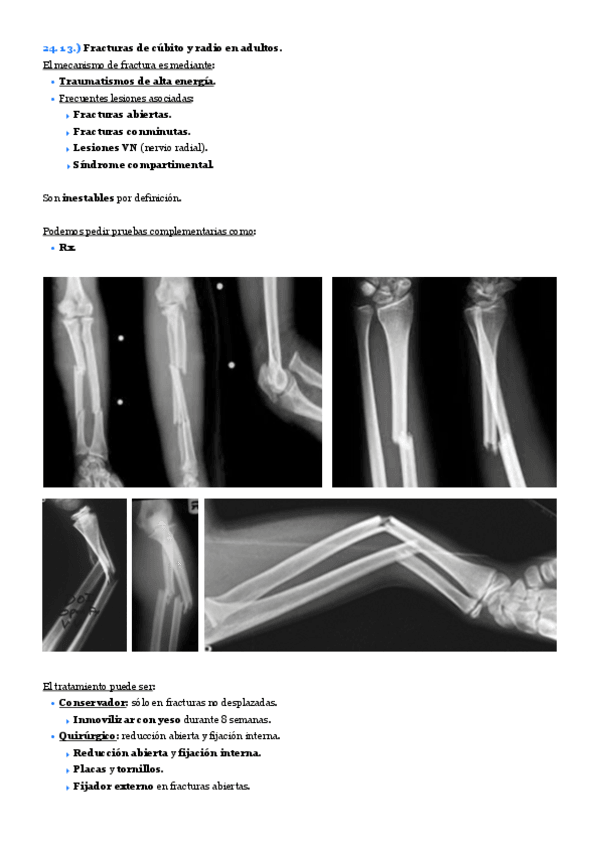

He publicado nuevos apuntes de 2º Patologia Médica y Farmacología I: Tema-24.-Patologia-traumatica-del-antebrazo-de-la-muneca-y-de-la-mano..pdf